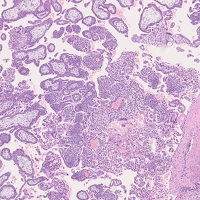

子宮内膜増殖症(複雑型)